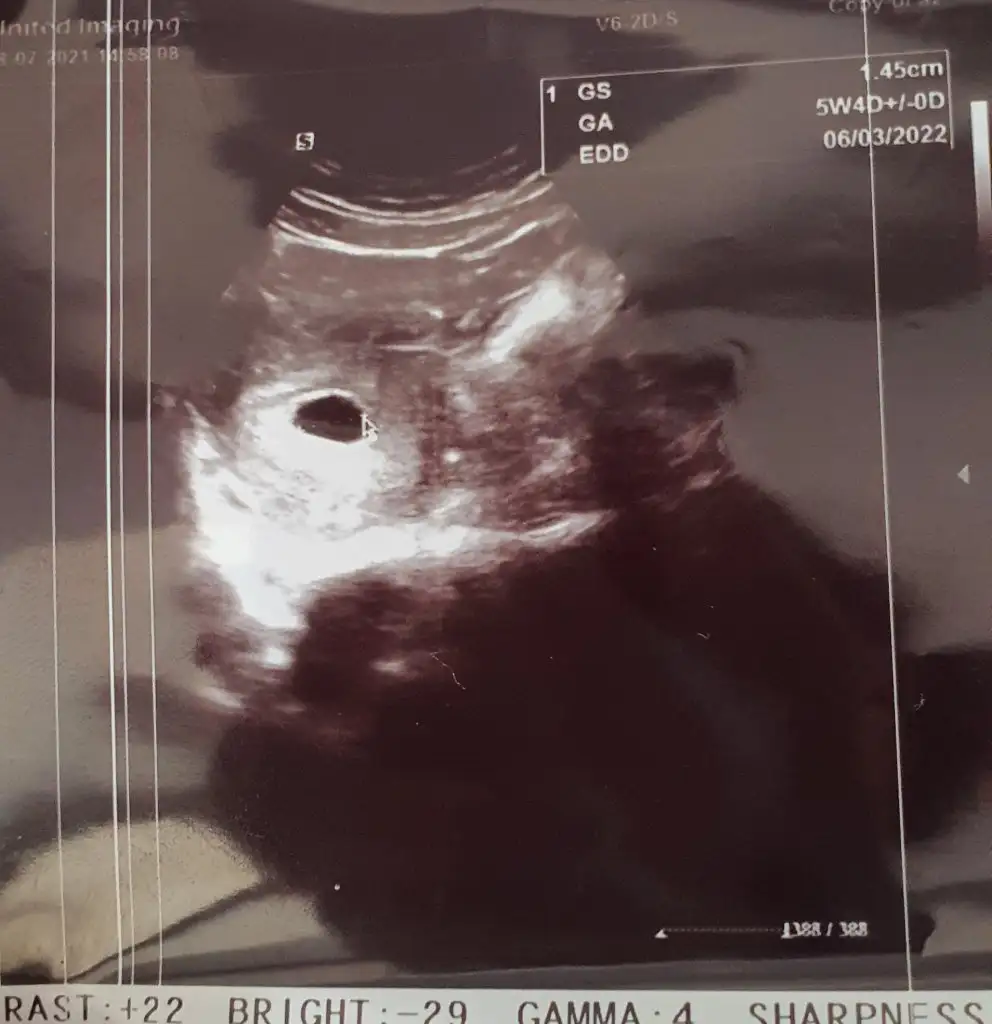

🌸1 temmuz beta 5639 canım yok normal keseyi geçen hafta gördü şubatta düşük yaptım açıkcası paniğim😥 bu ikinci gebelik yolk kesesi minikte olsa var dedi ama bebek göremedi e kalp atışı duyamadı dogal olarak çarşamba bakalım ne olacak? Üstüne 5+6 değil 5+4 çıkınca iyice üzüldüm dr pek takılmadı ona ama işte 🤷‍♀️hakkını helal et uzun oldu cnm

Ama kızımda 5. Haftada vajinal ultrasonla sadece keseyi görebilmiştik. 7. Haftada kalbini duymuştuk.

Ooo vajinal bakmadiysa hiç mi hiç sıkıntı yapma ne olur . Vajinalde anca gözükür bu haftada bebiş .bana 6+3 de keseyi görüyorum ama istersen vajinal bakalım daha iyi olur dedi tm dedim . Kalp atsina kadar gördü